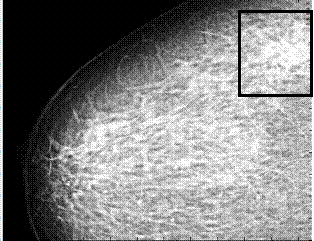

На рис. 1а представлена

маммограмма с непальпируемой онкологической опухолью (выделенный

прямоугольником фрагмент) в виде участка перестроенной структуры тканей

молочной железы с незначительным количеством микрокальцинатов. В других

областях традиционной маммограммы микрокальцинаты не видны. Однако на распределении

эффективного атомного номера (рис. 1б) микрокальцинаты проявляются весьма

отчетливо, что может свидетельствовать о мультицентрическом поражении тканей

молочной железы, по ходу млечных протоков. При этом видны и микрокальцинаты

размером

а б

в

Традиционная

маммограмма (а), нелинейные преобразования распределение эффективного номера

(б), увеличенный фрагмент (в)

Последующий морфологический

анализ этой удаленной молочной железы подтвердил наличие микрокальцинатов в

данных областях.